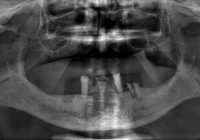

I casi complessi in implantoprotesi con connessione conometrica

Osteoconduzione, osteoinduzione, distrazione osteogenetica, GBR sono le procedure per rimediare alla carenza dei volumi ossei a livello dei mascellari. Con materiali da innesto osteoinduttivi e con materiali osteoconduttivi si favorisce il processo di aumento o rigenerazione dei volumi ossei, sia colmando difetti ossei post-estrattivi o da lesioni endodontiche, sia rigenerando volumi ossei con l’aiuto di membrane o griglie di titanio. Leggi »